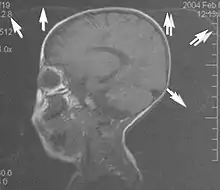

A wrap-around artifact also known as an aliasing artifact, is a result of mismapping of anatomy that lies outside the field of view but within the slice volume.[4] The selected field of view is smaller than the size of the imaged object. The anatomy is usually displaced to the opposite side of the image (Figs 6 and 7). It can be caused by non-linear gradients or by undersampling of the frequencies contained within the return signal.[1] The sampling rate must be twice the maximal frequency that occurs in the object (Nyquist sampling limit). If not, the Fourier transform will assign very low values to the frequency signals greater than the Nyquist limit. These frequencies will then ‘wrap around’ to the opposite side of the image, masquerading as low-frequency signals. In the frequency encode direction a filter can be applied to the acquired signal to eliminate frequencies greater than the Nyquist frequency. In the phase encode direction, artifacts can be reduced by an increasing number of phase encode steps (increased image time). For correction, a larger field of view may be chosen.[1]